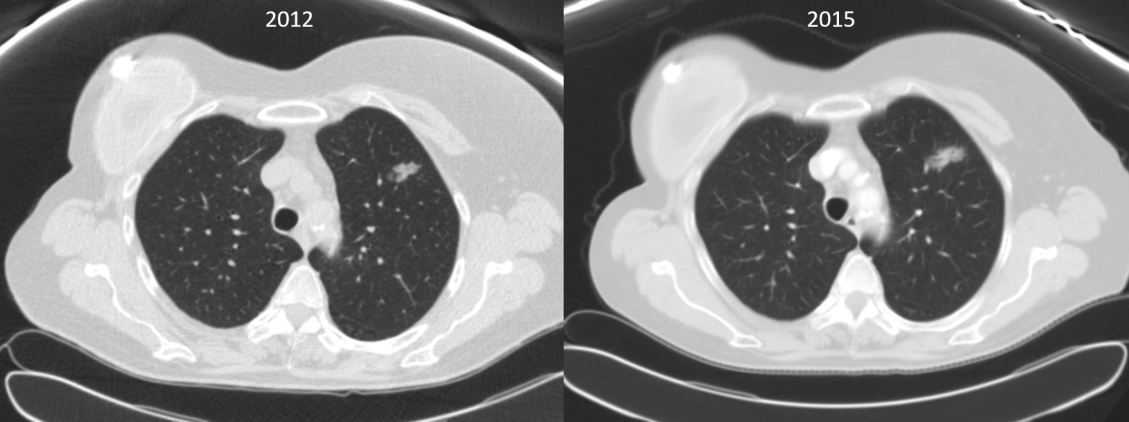

A 70-year-old woman with a past history of breast cancer in 2004 also had a nonperipheral pseudonodular ground glass appearance lesion in the left upper lobe since 2010, a core-needle biopsy in 2012 and 2015, and a diagnosis of benign pneumocytoma (Figure 1). Since 2018, the lesion had a growth of the solid component in chest computed tomography scan, so a positron emission tomography scan was performed, which showed an increased metabolic uptake in the lesion (SUV max 2.77) (Figure 2).

Figure 1